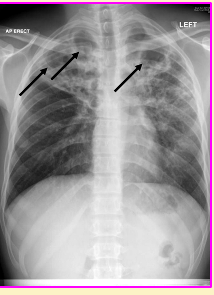

Dr de Silva, a junior doctor, spent 6 months working in a refugee camp in Thailand. She presents to her GP with fatigue, malaise and cough of one month's duration occasionally productive of rust-coloured sputum. Dr de Silva has also noted 3 kg weight loss in the last month. She does not smoke. Her GP arranges for a chest x-ray, image shown on the left. The radiologist phones the GP because she is concerned about the abnormalities shown by the arrows. **Q3a: What is the most likely diagnosis in this patient?** **Q3b: What type of abnormality(s) does the chest x-ray show? Describe in detail**. **Q3c: What are risk factors for the disease Dr de Silva most likely has? – list a minimum of three (they do not have to be specific to Dr de Silva).**

Dr de Silva, a junior doctor, spent 6 months working in a refugee camp in Thailand. She presents to her GP with fatigue, malaise and cough of one month's duration occasionally productive of rust-coloured sputum. Dr de Silva has also noted 3 kg weight loss in the last month. She does not smoke. Her GP arranges for a chest x-ray, image shown on the left. The radiologist phones the GP because she is concerned about the abnormalities shown by the arrows. Q3a: What is the most likely diagnosis in this patient? **Patient’s symptoms and chest x-ray suggest primary TB** Q3b: What type of abnormality(s) does the chest x-ray show? Describe in detail. **Ghon foci – little arrow; primary TB site Enlarged hilar lymph nodes – big arrow – together called a Ghon COMPLEX. Consistent with primary TB (vs reactivation TB)** Q3c: What are risk factors for the disease Dr de Silva most likely has? – list a minimum of three (they do not have to be specific to Dr de Silva). **Recent arrival or travel country where TB endemic Work in areas endemic for TB HIV Poorly controlled Type 2 Diabetes Mellitus Other immunocompromise states (i.e. cancer for which patient undergoing chemotherapy) Homeless Drug users, prison inmates Close contacts of patients with MTB disease**